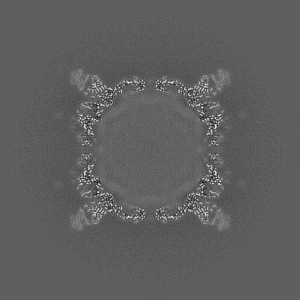

Cryo-EM structure of Coxsackievirus B1 A-particle in complex with nAb 8A10 (CVB1-A:8A10)

Single-particle3.19 Å